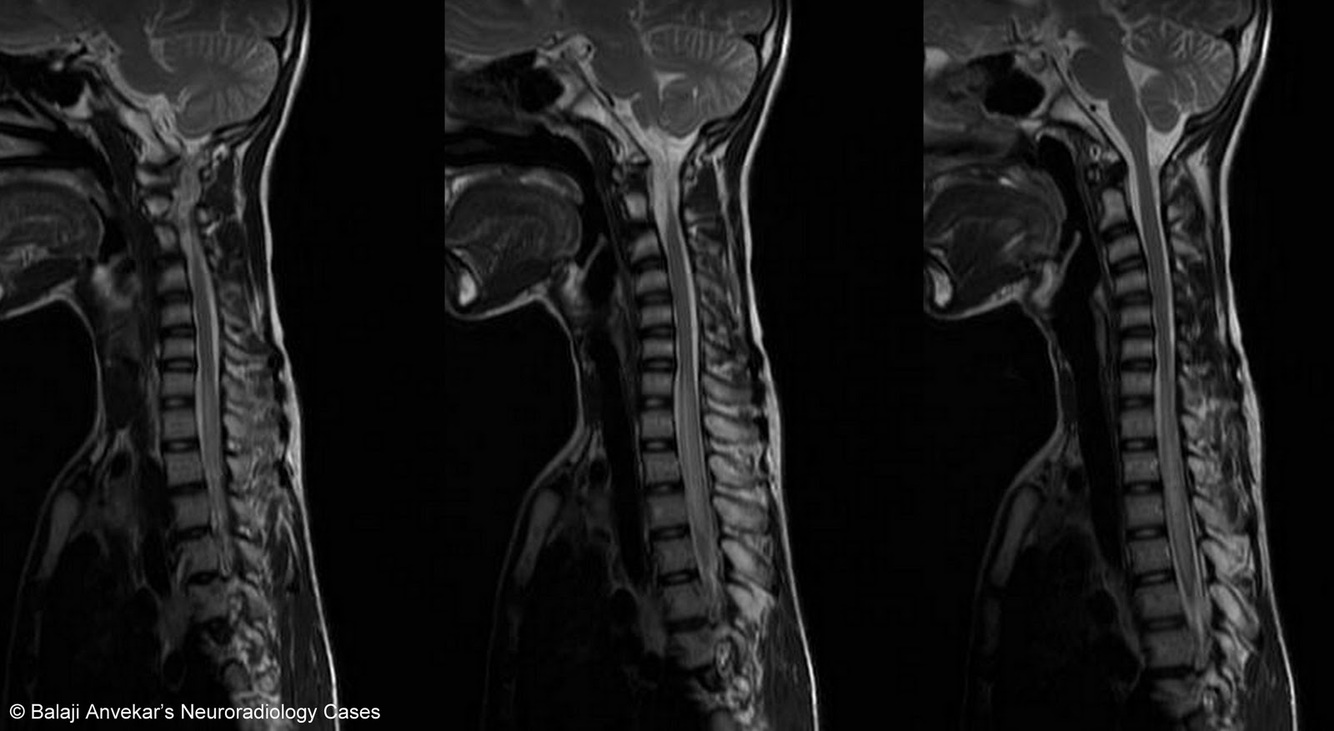

Intramedullary Multifocal Abnormal T2W Signal DDx

Acute Disseminated Encephalomyelitis (ADEM)

Etiology:

- Autoimmune process post predisposing infection (e.g. mumps, strep., Varicella) producing an inflammatory reaction

Key Fx:

- Multifocal white matter lesions with relatively little mass effect or vasogenic edema

- Flame-shaped lesions with slight cord swelling

- Anywhere in spinal cord white matter

- Variable enhancement, depending on stage of disease

- Brain almost always involved